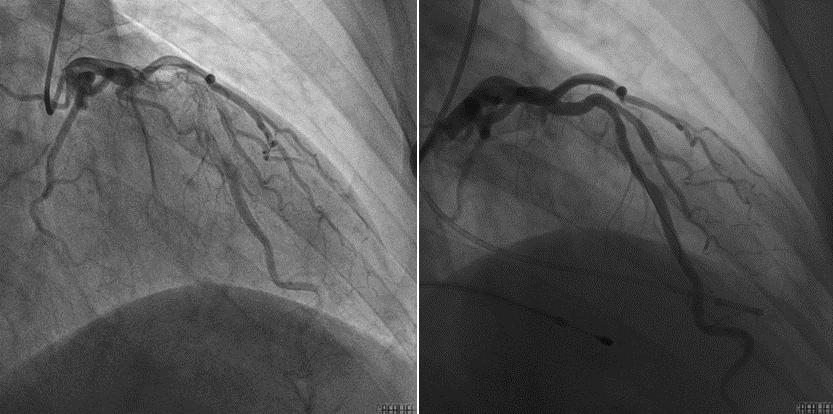

一根细导管,数个微小球,在心脏纵横交错的血管网络间精准“拆弹”,让不堪重负的心脏重获新生。近日,苏州大学附属第四医院心内科学科带头人周亚峰教授团队顺利为一名梗阻性肥厚型心肌病患者实施了“经皮室间隔心肌消融术(PTSMA+经皮腔内室间隔支微粒球栓塞术,该微创治疗技术在我院首次开展仅仅过去数月,现已实现常态化开展,步入成熟应用新阶段。

肥厚型梗阻性心肌病是一种遗传性心血管疾病,其特征为心肌肥厚、左心室流出道梗阻,可导致胸闷、呼吸困难,甚至晕厥和猝死。此次手术的患者病情发展已经使得日常活动已成为一种负担,轻微活动即诱发胸闷气短,疾病正不断侵蚀其生活质量。经我院心内科团队全面评估,患者左心室流出道存在严重梗阻,具有明确的手术指征。术中,苏大附四院心内科团队精准定位靶血管,确保微粒球精准作用于梗阻区域,通过物理方式堵塞供应肥厚心肌的血管,使其自然萎缩,从而解除梗阻。